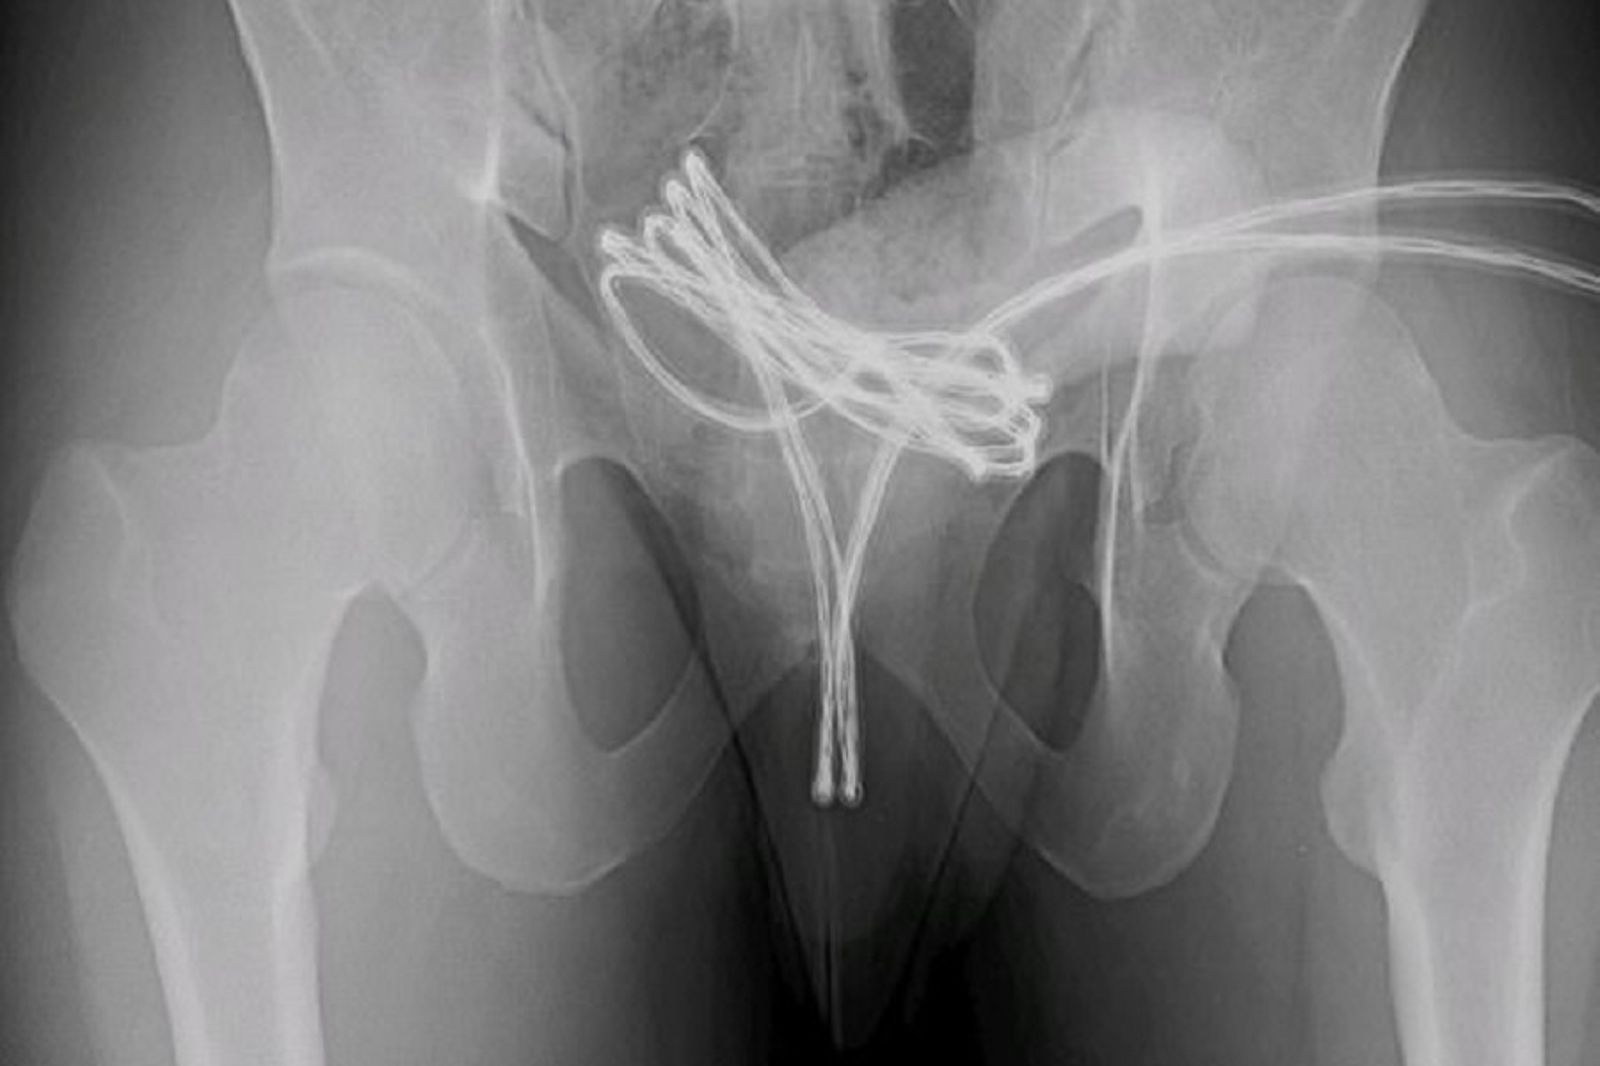

醫學期刊《Cureus》近日刊登一起美國醫師的報告案例,一名21歲男子掛急診,原因竟是整條USB線卡在下體,並纏住膀胱。男子也承認,自己和這條USB線有過激烈愛愛。

報告指出,這名男子掛急診時,被檢查出一條長長的USB線已經穿過尿道,進入了膀胱,甚至快要纏住膀胱。醫師本來試圖徒手取出,但後來發現無法成功,因此只好先將男子麻醉,利用醫療工具將這條USB線取出。最後醫師成功將USB線取出,並讓男子住院1週觀察,待男子狀況穩定後,讓男子回家休養,並開立止痛藥與抗生素給男子服用。

男子之後持續回診,身體恢復狀況良好,治療後1個月再檢查,醫師發現男子的狀況已無大礙。男子承認,自己過去就有把棉花棒、電纜電線插入下體的前例,而這次是和USB線愛愛,但沒想到「無可自拔」。

醫師指出,出於性或其他原因將物體自行插入尿道的情況,並不常見,但可能會造成嚴重傷害,已知的風險包括感染,感染會對生殖器官造成永久性損害,進而導致危及生命的敗血症。如果插入的物體到達膀胱,也有可能造成膀胱破裂。